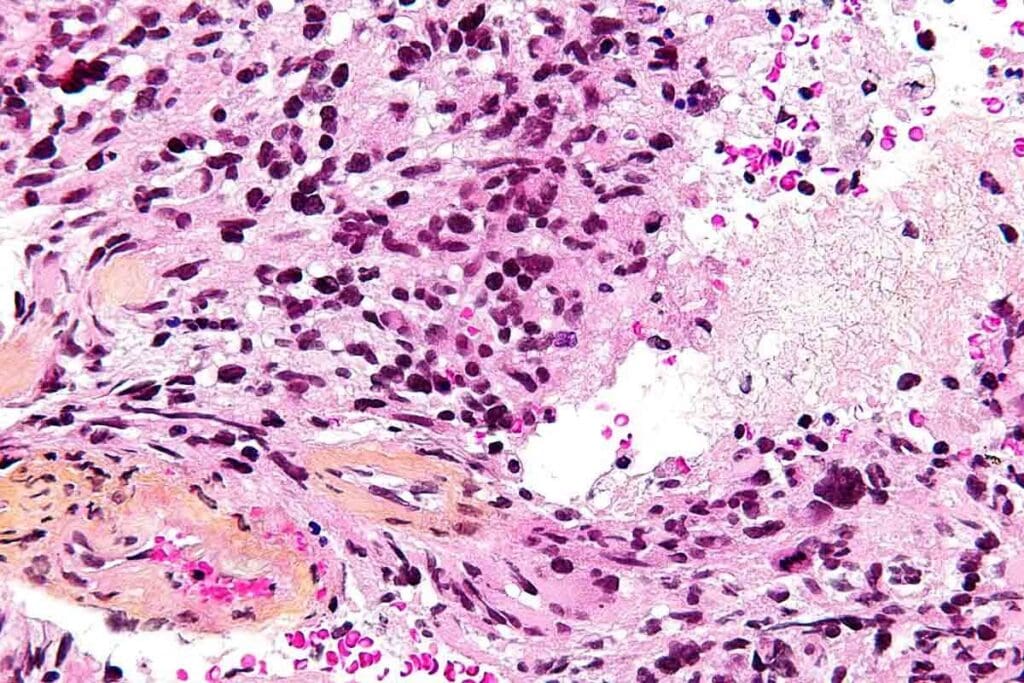

Biopsy and Histopathological Evaluation

A biopsy is key to confirming GBM. We take tissue samples during surgery. Looking at these samples under a microscope helps us spot the tumor’s unique features.

Cellular and Molecular Characteristics

Pediatric glioblastoma multiforme grows fast and is very aggressive. It has many cell types, including stem-like cells. These cells help the tumor fight off treatmentsas studies show.

The tumor’s genes and epigenes change a lot. These changes mess with signals that control cell growth and survival. For example, TP53 and PTEN gene mutations are common in GBM, making it very bad.